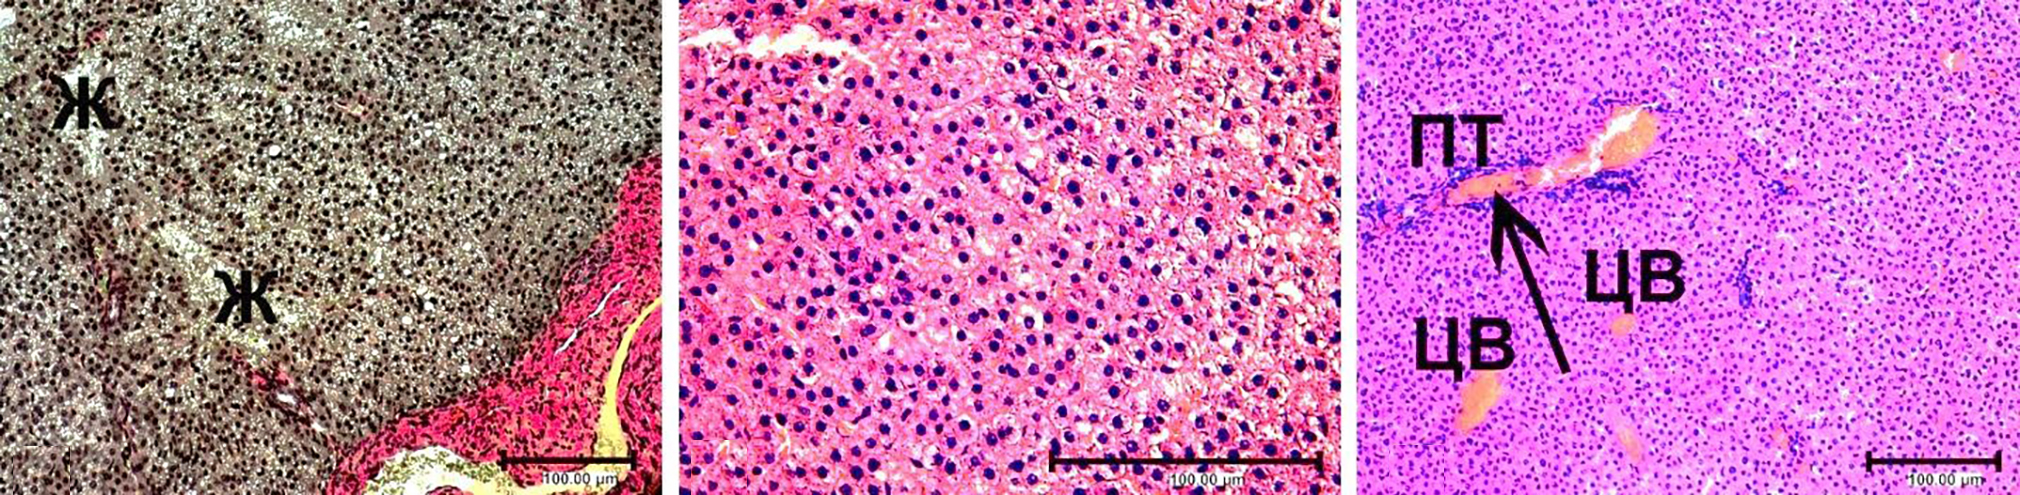

При субхроническом отравлении беременных крыс экотоксикантами на препаратах печени крысят, рождённых от них впоследствии, определялись выраженные дистрофические изменения гепатоцитов в разных участках паренхимы: как по периферии печёночных долек, так и вокруг портальных трактов. Часто эти изменения выражались в сильной вакуолизации или просветлении цитоплазмы клеток, что свидетельствовало о жировой или гидропической дистрофии клеток соответственно. На рис. 1, a можно увидеть участок жирового перерождения паренхимы.

Полиморфные гепатоциты теряли правильную трабекулярную архитектонику, характерную для строения печени в норме, располагались хаотично, беспорядочно (рис. 1, b). Большинство ядер печеночных клеток выглядели плотными, базофильно окрашенными. Иногда выявлялись участки паренхимы с разрушающимися гепатоцитами. Во многих местах в расширенных синусоидных капиллярах определялся выраженный гемостаз (рис. 1, c).

Отдельные перипортальные зоны инфильтрировались воспалительными клетками (см. рис. 1, b, c). Большей частью это были скопления крупных макрофагальных клеток с тёмным базофильным ядром и цитоплазмой или округлых тёмных лимфоцитов, что хорошо видно на рисунке. Большинство центральных вен были расширены и кровенаполнены (проявления гемостаза), так же как и кровеносные сосуды портальных трактов (рис. 1, d). Происходило набухание и утолщение соединительнотканной стромы печени, особенно вокруг портальных трактов. Такая патоморфологическая картина характерна для гепатозов, переходящих в хронический токсический гепатит.

Рис. 1. Структура печени крысы контрольной группы, окраска гематоксилином и эозином: a — в области портального тракта — вакуолизация гепатоцитов, потеря трабекулярного строения паренхимы; ×100; b — в области портального тракта — дистрофические изменения гепатоцитов (↑), макрофагальная инфильтрация (↑↑), потеря трабекулярного строения паренхимы; ×200; c — клеточные инфильтраты (↑), гемостаз в расширенных синусоидах (↑↑), потеря трабекулярного строения паренхимы; ×200; d — гемостаз в цен- тральных венах и сосудах портальных трактов (↑); ×100. Здесь: ПТ — портальный тракт, Ж — участок жирового перерождения, ЦВ — центральные вены.

Fig 1. The structure of the liver of a rat in the control group, stained with hematoxylin and eosin: a — in the area of the portal tract — vacuolization of hepatocytes, loss of the trabecular structure of the parenchyma; ×100; b — in the area of the portal tract — dystrophic changes in hepatocytes (↑), macrophage infiltration (↑↑), loss of the trabecular structure of the parenchyma; ×200; c — cellular infiltrates (↑), hemostasis in dilated sinusoids (↑↑), loss of the trabecular structure of the parenchyma; ×200; d — hemostasis in the central veins and vessels of the portal tracts (↑); ×100. Here: ПТ — portal tract, Ж — area of fatty degeneration, ЦВ — central veins.